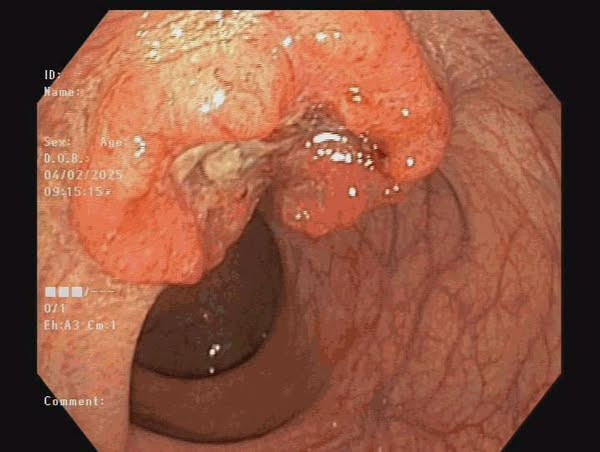

Người bệnh là nữ (72 tuổi, trú tại Quỳnh Phụ, Thái Bình) đến viện vì lý do đại tiện phân có dây máu, mót rặn. Tiến hành thăm khám và thực hiện nội soi đại trực tràng phát hiện: trực tràng ngay trên ống hậu môn, cách rìa hậu môn 3cm có u sùi kích thước 20mm.

Tiến hành xét nghiệm sinh thiết kết quả là ung thư biểu mô tuyến. Người bệnh được phẫu thuật nội soi cắt đoạn đại trực tràng nạo vét hạch, nối đại tràng ống hậu môn.

| Khối u của bệnh nhân trên phim chụp - Ảnh BVCC |